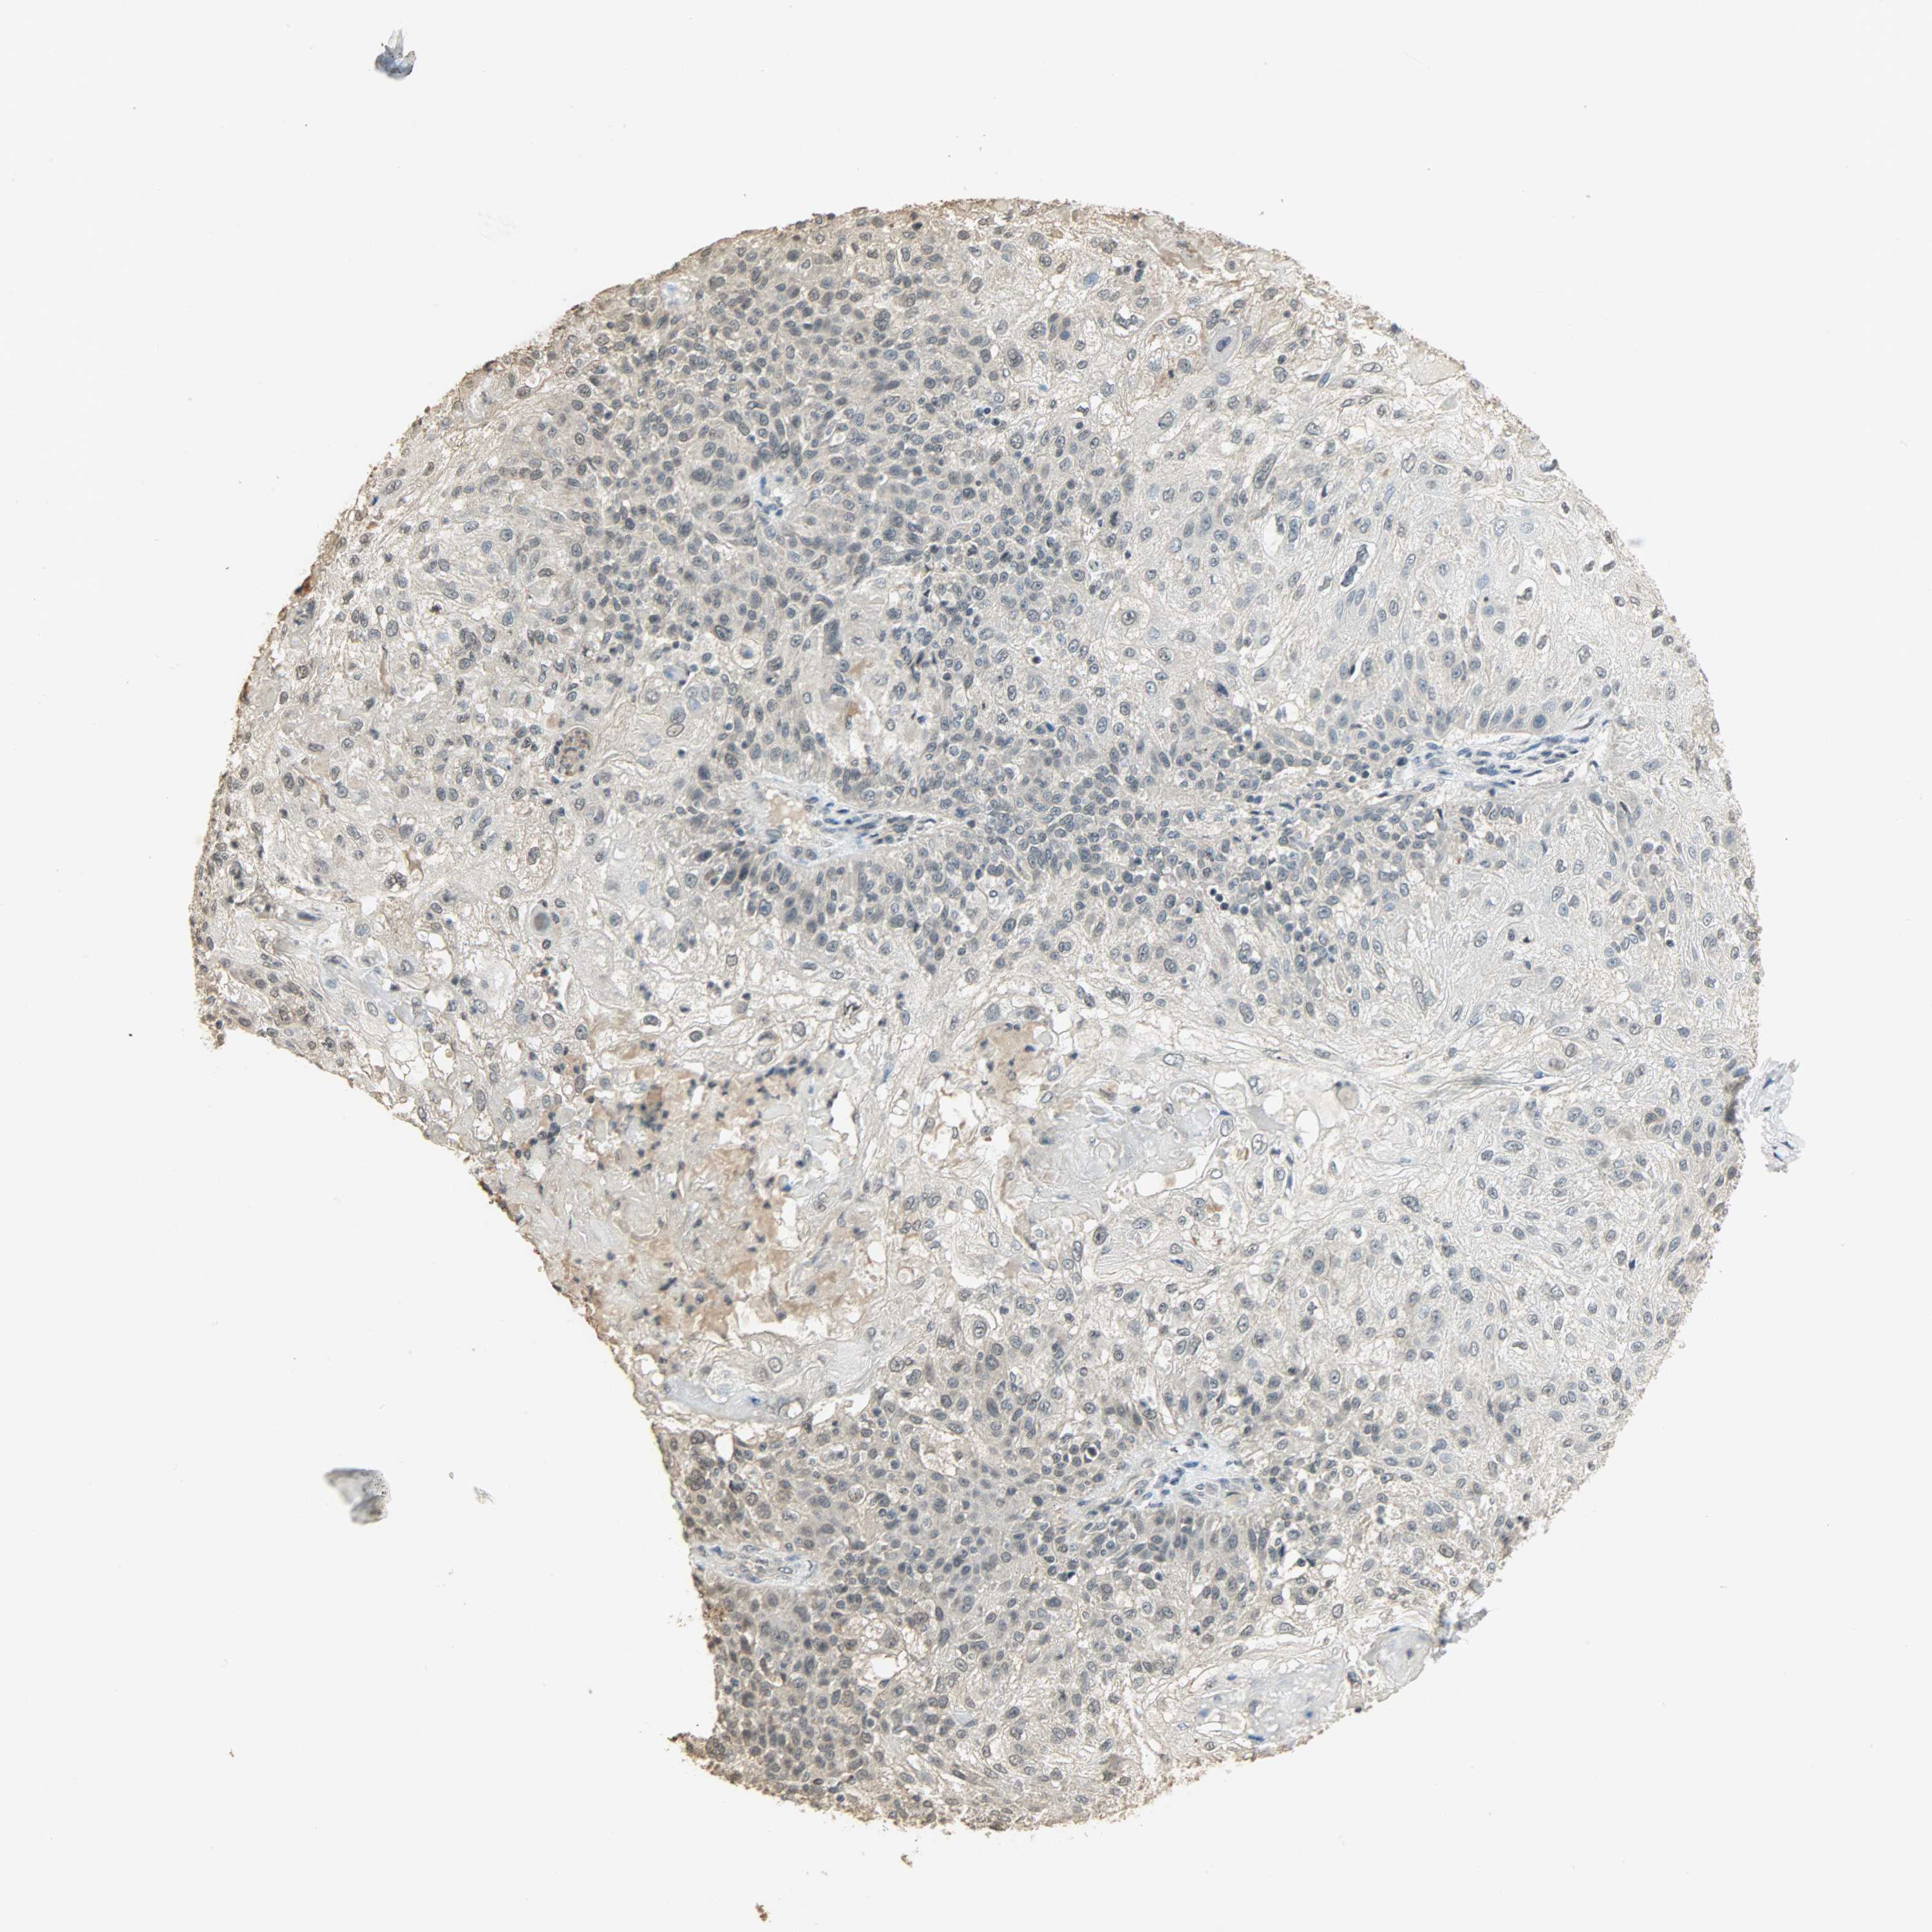

SKIN CANCER - Protein expressioni

A mouse-over function shows sample information and annotation data. Click on an image to view it in a full screen mode. Samples can be filtered based on level of antibody staining by selecting one or several of the following categories: high, medium, low and not detected. The assay and annotation is described here.

Antibody stainingi

Antibody staining in the annotated cell types in the current human tissue is reported as not detected, low, medium, or high, based on conventional immunohistochemistry profiling in selected tissues. This score is based on the combination of the staining intensity and fraction of stained cells.

Each image is clickable and will lead to virtual microscopy that enables deeper exploration of all samples and also displays staining intensity scores, fraction scores and subcellular localization as well as patient and tissue information for each sample.

Antibody HPA008751

Antibody CAB005227

Staining

Not detected

Negative

None

Squamous cell carcinoma, NOS